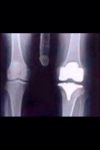

You may not have heard but I have recently had to have my left knee replaced.

It was all a bit sudden but I was getting quite a bit of pain.

The Specialist said it was arthritis caused by old Rugby injuries and prospecting.

I am still on crutches, it is a lot better and I no longer have any stiffness.

The Hospital has sent me a copy of my XRay of the replacement..below....and all looks better than most.....

All better.jpg..Hoo Roo.....eat your heart out Jim....